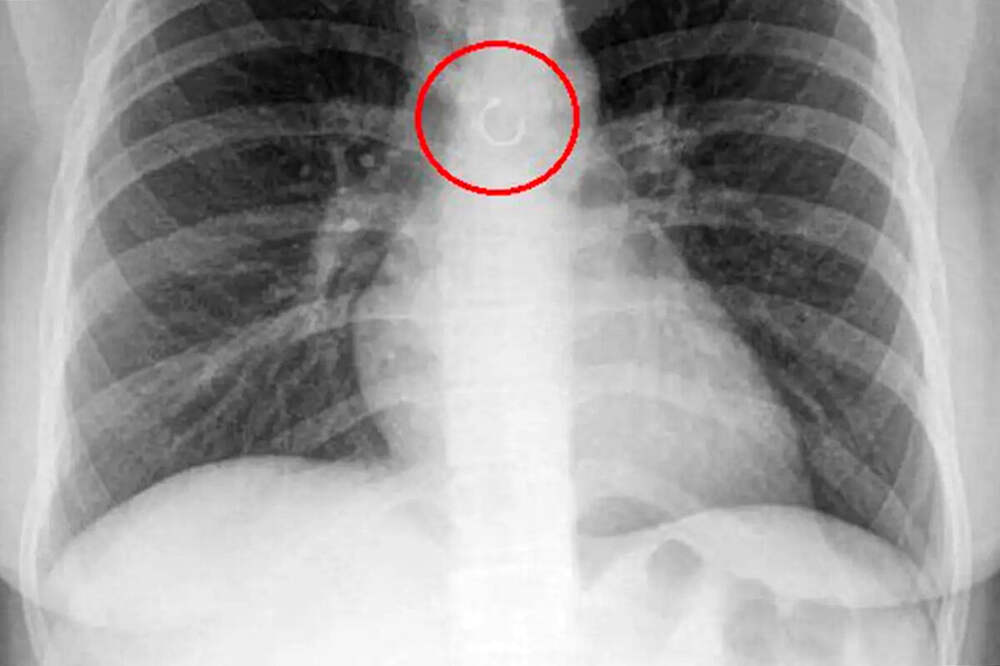

В Мексике женщина обнаружила, что потерянное кольцо в носу попало в ее легкие, пишет Fox News. По словам Моники Барахас, она долгое время думала, что кашель связан с погодой или простудой. Лишь спустя больше месяца, когда симптомы не проходили, она обратилась к врачу. Во время обследования... Далее